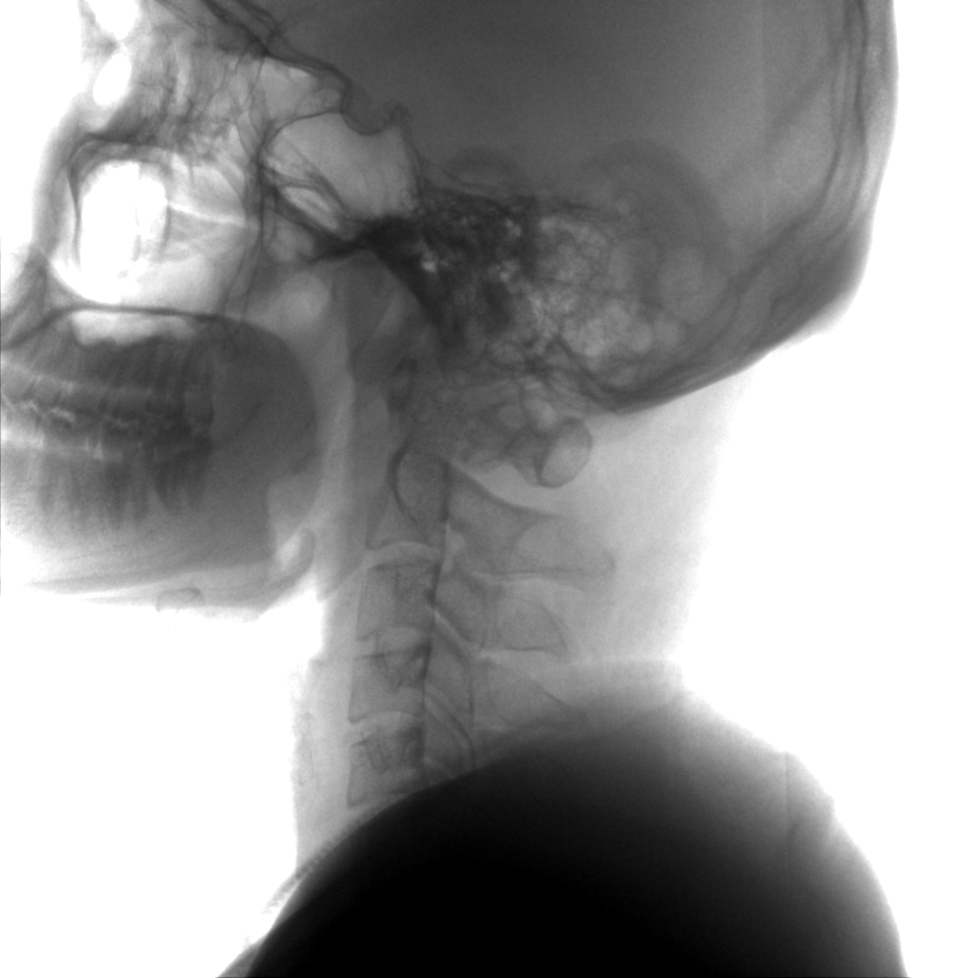

成像清晰、操作簡易、擺位便捷,主要適用于骨科、脊柱外科、矯形外科、創(chuàng)傷骨科及手術(shù)室等,能大幅度提升手術(shù)水準(zhǔn),降低手術(shù)風(fēng)險和并發(fā)癥的概率。

提供更大的術(shù)中三維成像視野,采集更多圖像信息,可一次拍全全段頸椎、全段腰椎、七節(jié)胸椎、雙側(cè)骶髂關(guān)節(jié)、股骨頭及單側(cè)盆骨。